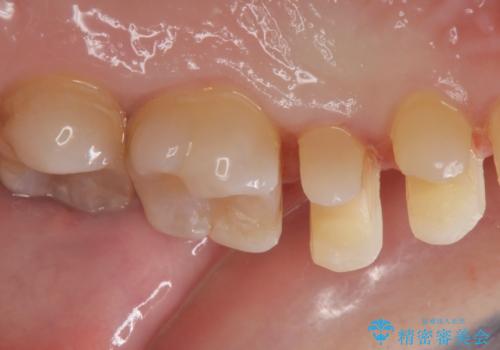

- 矯正前の患者様です。検査をしたところ虫歯が見られたので拡大鏡下で虫歯を取り除き

e-maxインレーで治療を行いました。

虫歯が多数ありましたのでまずは2本虫歯治療を行いました。